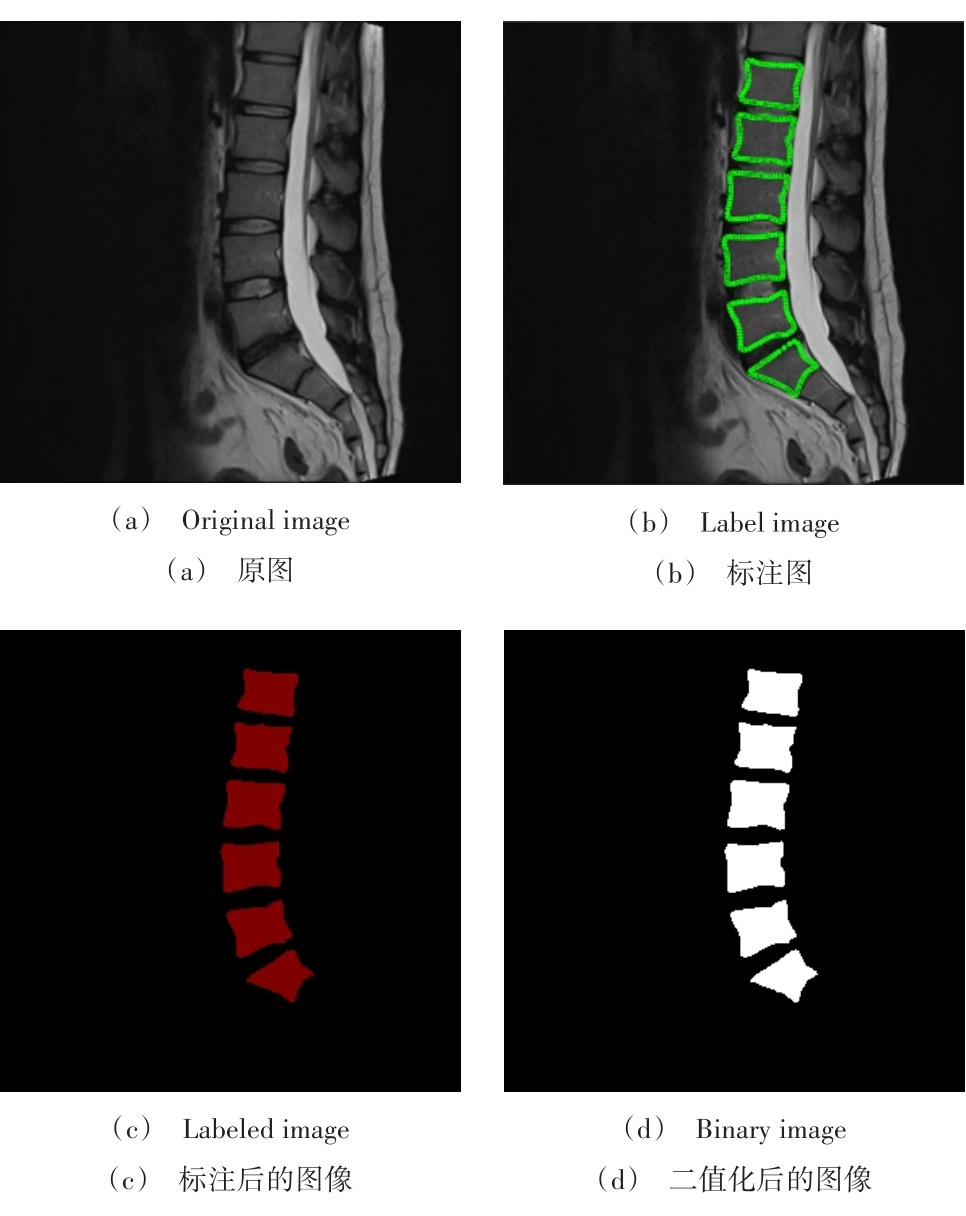

首先,在来自矢状位MR T2加权图像的54个病例中选择出用于训练的数据集共包含44组样本,并将剩余10组分别用作测试和验证用例。随后,在Labelme软件中对训练集进行椎骨区域的标注(如图4所示)。最后将图像进行二值化处理(如图4b所示),并将其作为模型训练的标签。整个标注过程在专业医师监督下完成,并确保所有处理后的图像尺寸一致(均为320×320像素),且深度保持在8位。

下载: | 高精图 | 低精图

图4 数据集标注过程示意

Fig. 4 Schematic diagram of the dataset annotation process